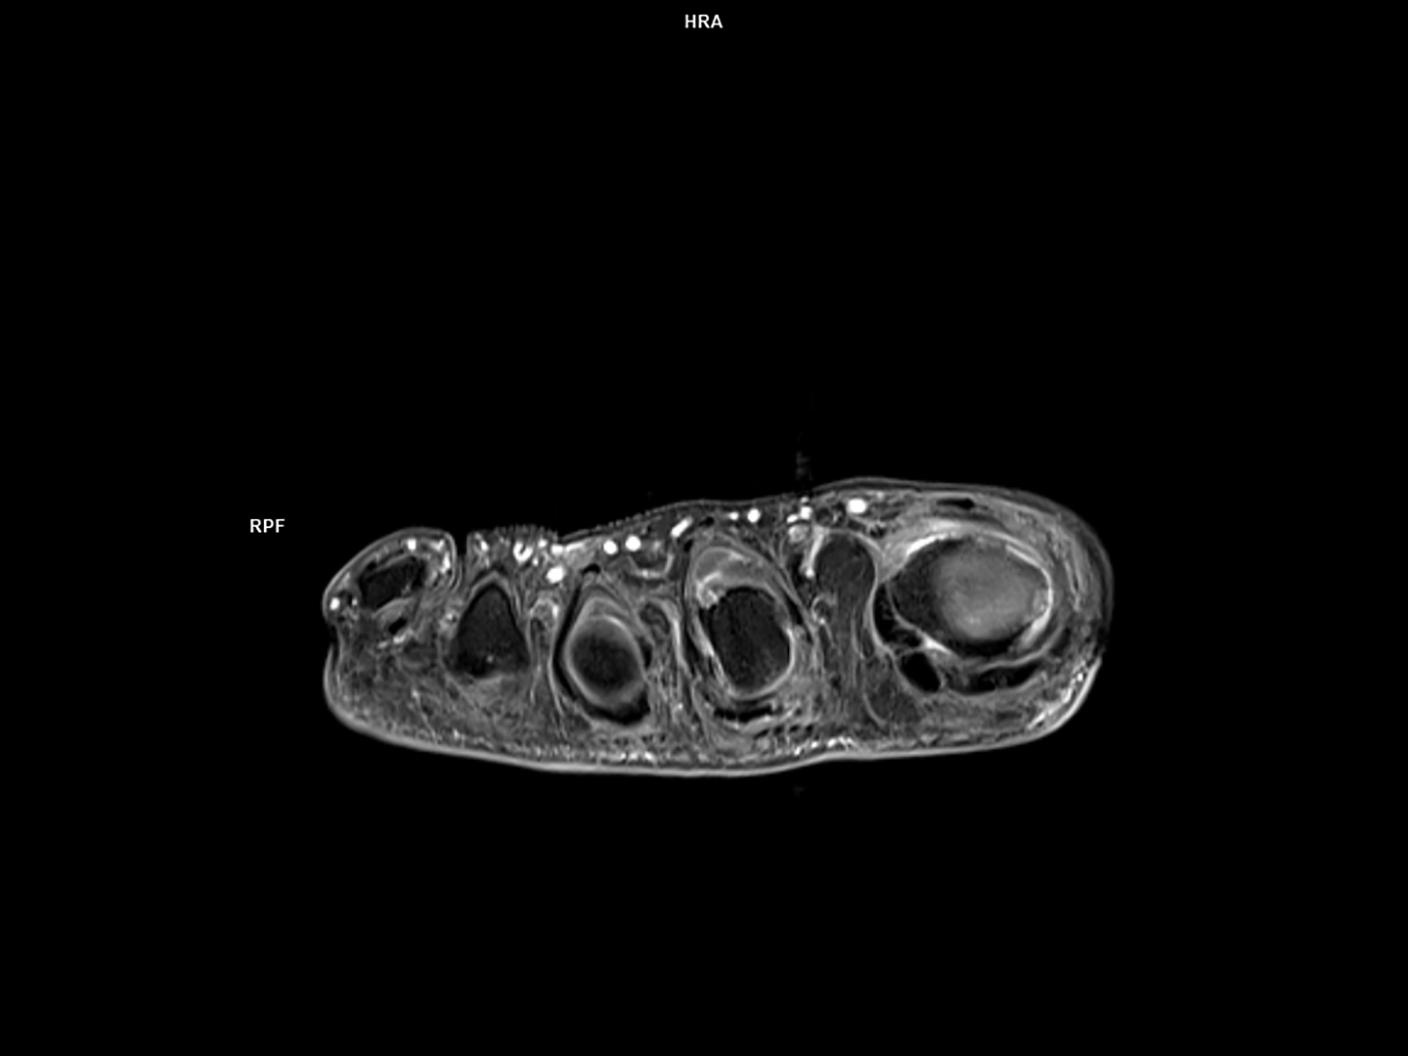

Axial T1 FS-MAGNETOM Vida

Axial T1 FS-MAGNETOM Vida/Coil-Foot Ankle 16/Resolution-384